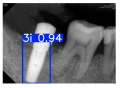

| Image Resolution = 825 × 1200 | ||||

|---|---|---|---|---|

| Test Image 1–4 | ![]() | ![]() | ![]() | ![]() |

| Accuracy | 94.13% | 95.29% | 92.88% | 91.80% |

| Recall | 96.71% | 94.03% | 93.88% | 92.15% |

| Model reference time | 6.57 ms | 7.08 ms | 7.12 ms | 6.43 ms |

| Dentists’ average diagnostic time | 2.78 s | 4.55 s | 7.78 s | 7.23 s |